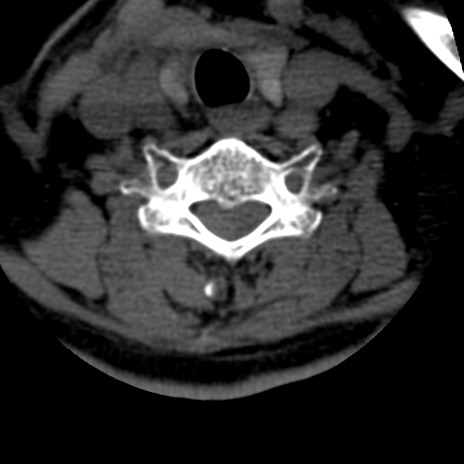

症例50 頚椎CT(横断像)

頚椎CT